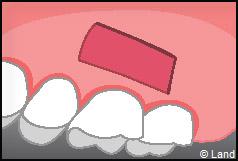

LES TECHNIQUES AVEC APPORT DE GENCIVE OU « GREFFE DE GENCIVE » :

Elles font appel à un prélèvement sur le patient à un endroit où elle est en excès, qui est ensuite posé sur la récession.

Les greffes épithélio-conjonctives :

Elles sont pratiquées pour des zones non esthétiques de la cavité buccale, à cause de l’aspect « rustine» que la cicatrisation leur confère.